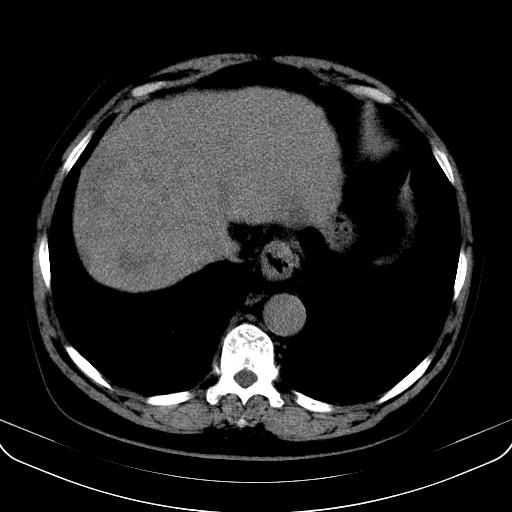

以下是引用jia119在2008-3-5 13:31:00的发言:[br]肝内多发片状低密度影,密度不均,我还是考虑肝ca可能,另肝内小囊肿,胆囊增大。

以下是引用形影不离在2008-3-5 12:18:00的发言:[br]肝硬化伴门脉高压征,肝内占位待排,增强再说.

以下是引用随光逐影在2008-3-5 21:11:00的发言:[br]肝硬化伴门脉高压(食管下段静脉曲张),肝癌不排除。建议:行ct增强扫描检查。

以下是引用同在2008-3-5 13:56:00的发言:[br]考虑肝癌可能性大,胆囊增大.